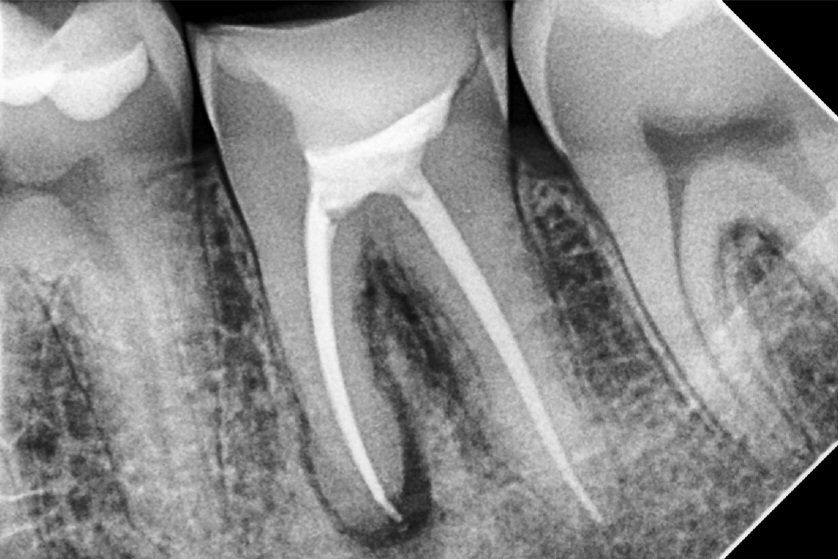

4. Filling the Canals

The clean canals are filled with a biocompatible material called gutta-percha, and sealed to prevent reinfection.

5. Restoration

The tooth is then sealed with a temporary or permanent filling. In most cases, a crown is recommended afterward to strengthen and protect the treated tooth, especially in the back of the mouth.